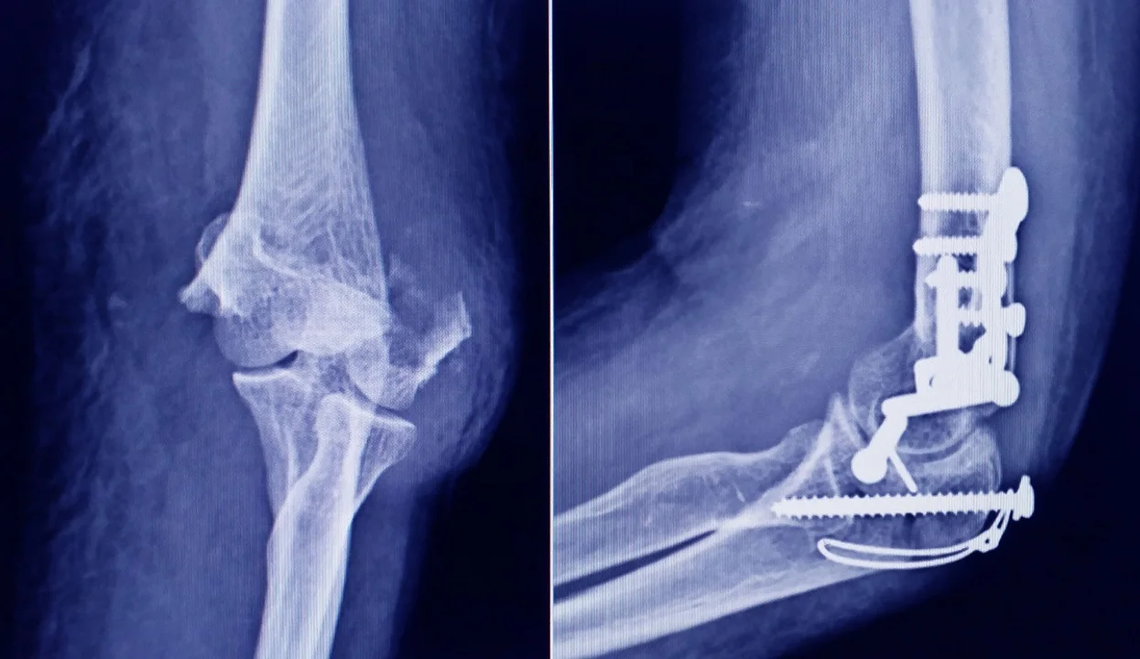

La Administración Nacional de Medicamentos, Alimentos y Tecnología Médica (ANMAT) emitió una alerta dirigida a la población por la detección de un tornillo apócrifo utilizado en cirugías traumatológicas, cuyo uso podría implicar un serio riesgo para la salud de los pacientes en los que sea implantado.

Según se informó, el tornillo corresponde a un producto que debería ser fabricado por Stryker Corporation, empresa registrada ante la ANMAT bajo el PM 594-139. Tras la inspección, la muestra recolectada fue exhibida a la responsable técnica de la compañía, quien confirmó que se trataba de una falsificación.

STRYKER 10 mm x 28 mm – Bioabsorbable – ACL Interference Screw – REF 234-010-067 – Lote 90905.